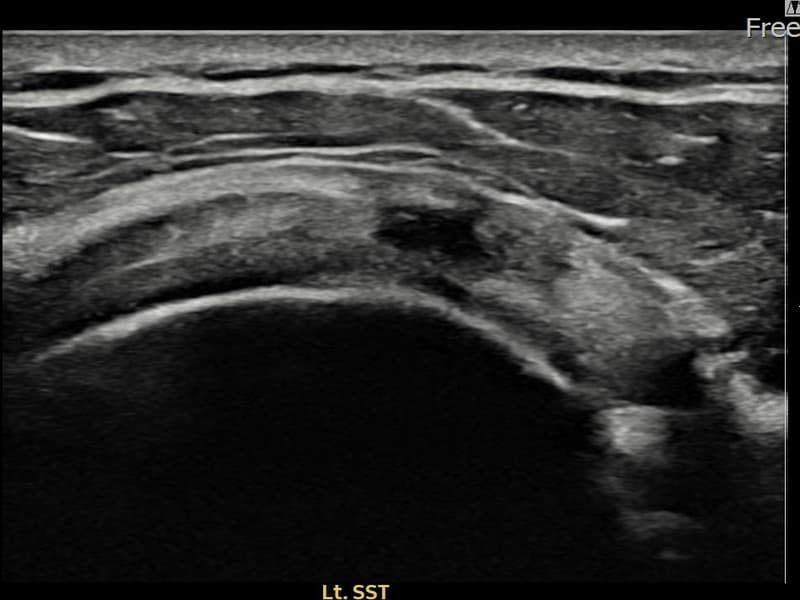

시술 전 초음파 측정 결과 파열 크기는 8mm × 3mm (힘줄 두께의 약 33% 결손)로 확인되었습니다. 시술 전 초음파에서 좌측 극상근건 관절면측의 에코 단절과 힘줄 내 저에코 결손이 확인되었습니다. 시술 후 초음파에서 파열 부위가 재생 조직으로 채워지고 힘줄 에코 패턴이 정상화된 것이 관찰되었습니다.

60대 중반 남성 환자분으로, 왼쪽 어깨 통증이 수개월간 지속되다가 최근 야간 통증까지 생겨 내원하셨습니다. 활동적인 생활을 즐기시는 분으로 통증으로 인해 운동이나 취미 활동에 제약이 생기셔서 비수술 치료를 강력히 원하셨습니다. 초음파 검사에서 좌측 극상근건 관절면측 부분파열이 확인되었으며, 초음파 유도 하 축소봉합술을 시행하였습니다. 시술 후 단계적으로 재활 운동을 진행하였고, 10주 후 추적 초음파에서 파열 부위가 재생 조직으로 채워지고 힘줄 연속성이 회복되어 정상 생활에 복귀하셨습니다.